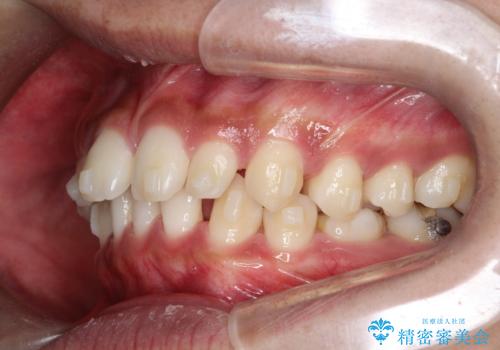

【インビザライン】空隙歯列の矯正

- 前歯の隙間を主訴に来院されました。

なるべく目立たない治療を希望されましたので、インビザラインにて治療を行なっております。

単純に前歯の隙間の閉鎖をしてしまうと、前歯に早期接触が生まれ、臼歯が噛まなくなってしまいます。適切な治療計画を立てることで、噛み合わせも良好な結果を得ることができました。